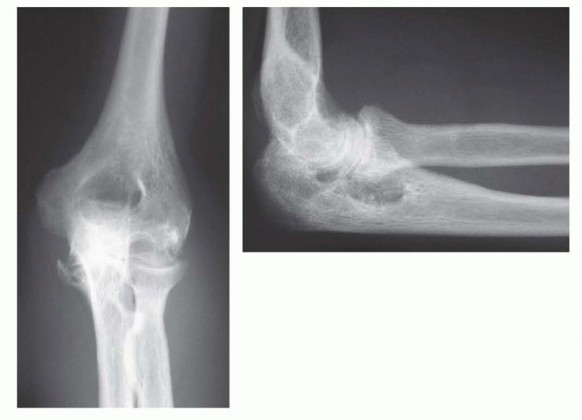

Surgical Management of Traumatic Conditions of the Elbow: Interposition Arthroplasty